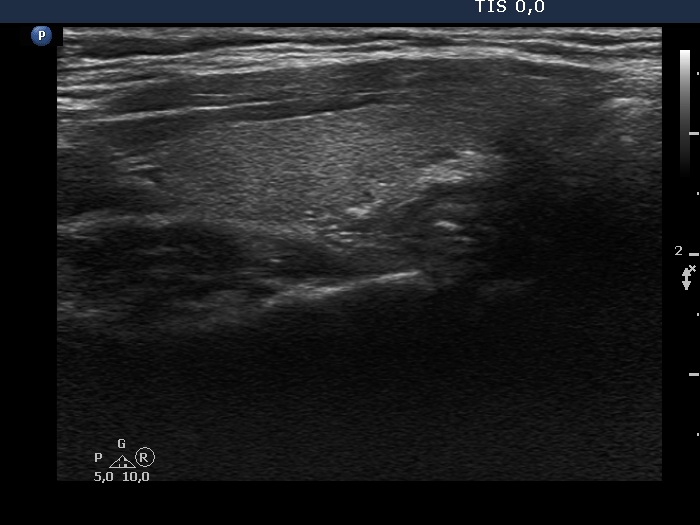

Discrete lesion or nodule in Hashimoto's thyroiditis - case 26 (1048)

Second examination three years later (ultrasonographic picture 6)

Left lobe longitudinal scan. The lower part of the lobe became moderately hypoechogenic.